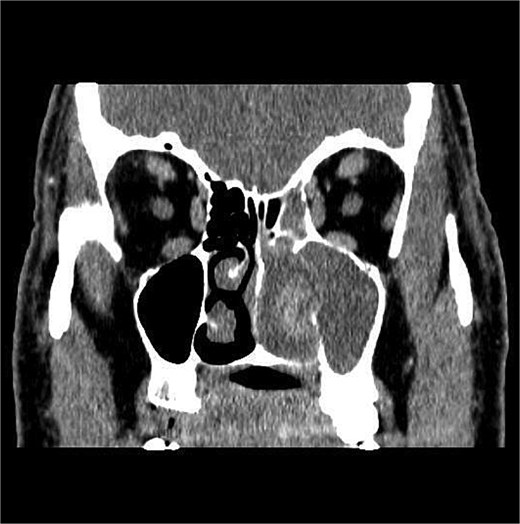

CT showed a heterogeneously enhancing mass completely occluding the left nasal cavity, left ethmoidal, maxillary and frontal sinuses, extending to left pterygopalatine fossa. It is associated with bony erosion of the posterior nasal septum and the left medial maxillary wall (Figs 1 and 2). Findings were suggestive of inverted papilloma vs sinonasal malignancy. Therefore, biopsy was recommended.

Coronal section of CT paranasal sinus with contrast bone window showing the bony erosion in the nasal septum and maxillary sinus wall.